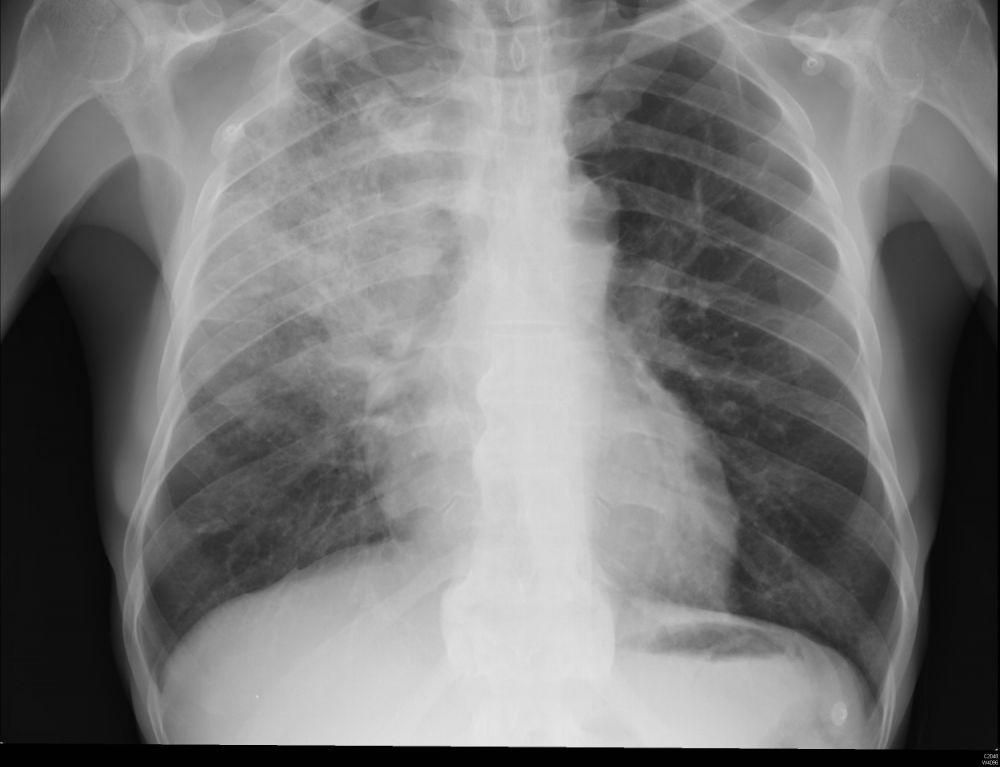

Pneumonia merupakan peradangan pada kantung udara kecil di dalam paru-paru, yang dikenal sebagai alveoli. Kantung udara ini terisi oleh nanah atau cairan, dan tingkat keparahannya bisa bervariasi dari ringan hingga serius, bergantung pada beberapa elemen seperti usia penderita dan jenis pneumonia yang dialami.

Mengetahui jenis pneumonia akan membantu dokter karena memengaruhi pengobatannya. Pneumonia dikelompokkan dalam tiga kategori besar yang meliputi pneumonia berbasis bakteri, infeksi jamur, dan virus.